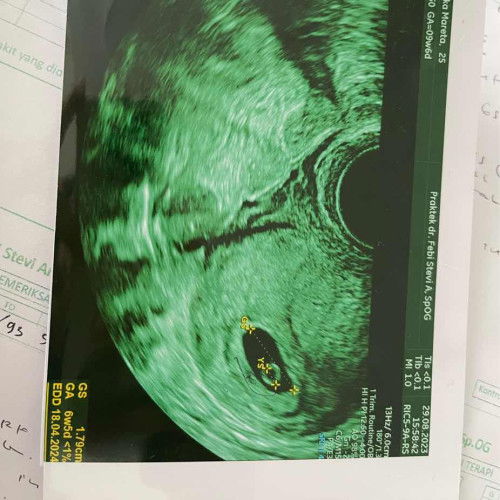

Setelah flek dari tanggal 27 agustus, dan pendarahan tgl 7 september, aku USG hari ini, dan kata dokter kehamilan ku tidak berkembang, bahkan tidak ada janin didalamnya, aku didiagnosa BO atau hamil kosong Biaya kuret diperkirakan 3.500 kalau umum di klinik dokter SPOG nya 🥹 Doakan kuretnya berjalan lancar dan aku segera hamil lagi ya bund aamiin Semangat bunda bunda yang sedang memperjuangkan garis 2, arau sedang hamil semoga sehat selalu 🥹🥰🙏#ikhlas